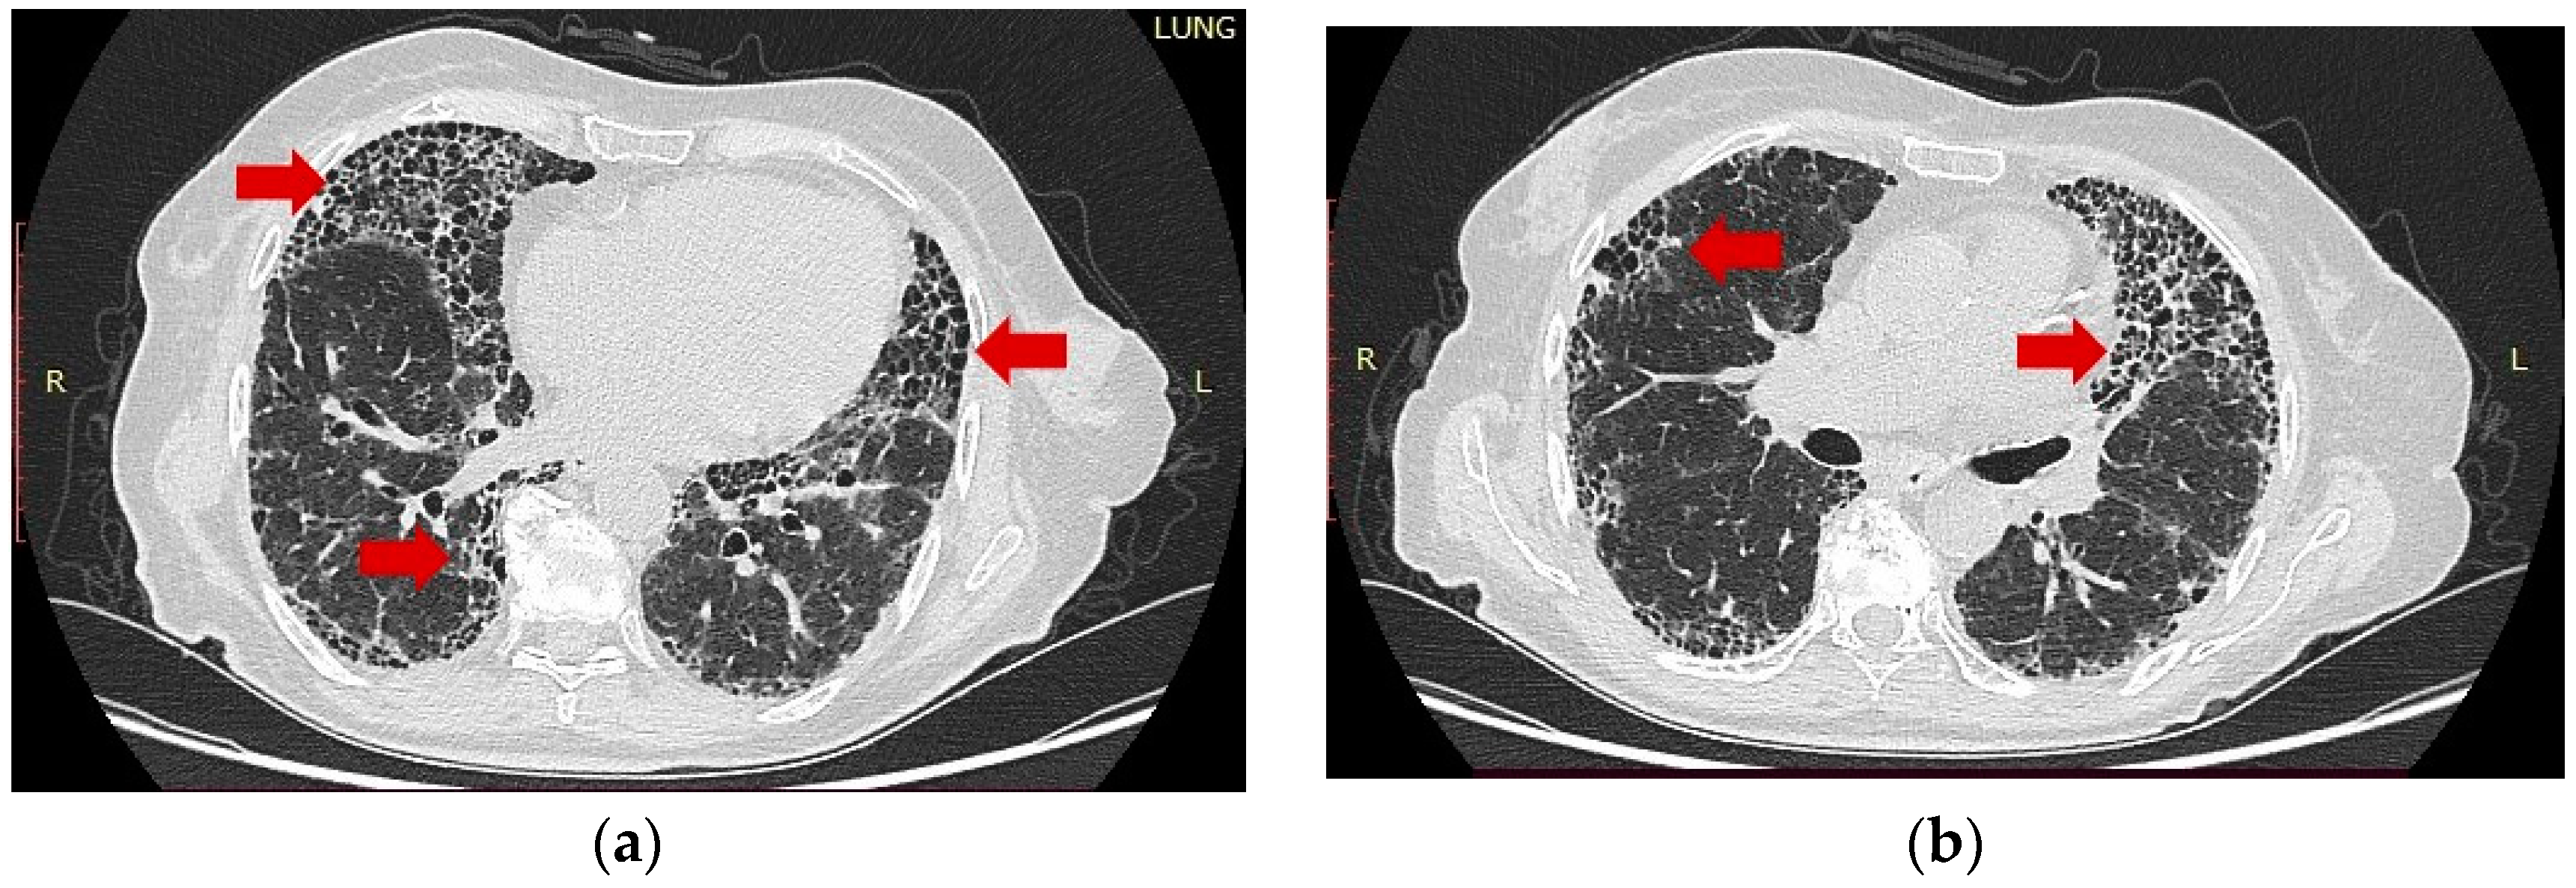

2.4. HR-CT Findings